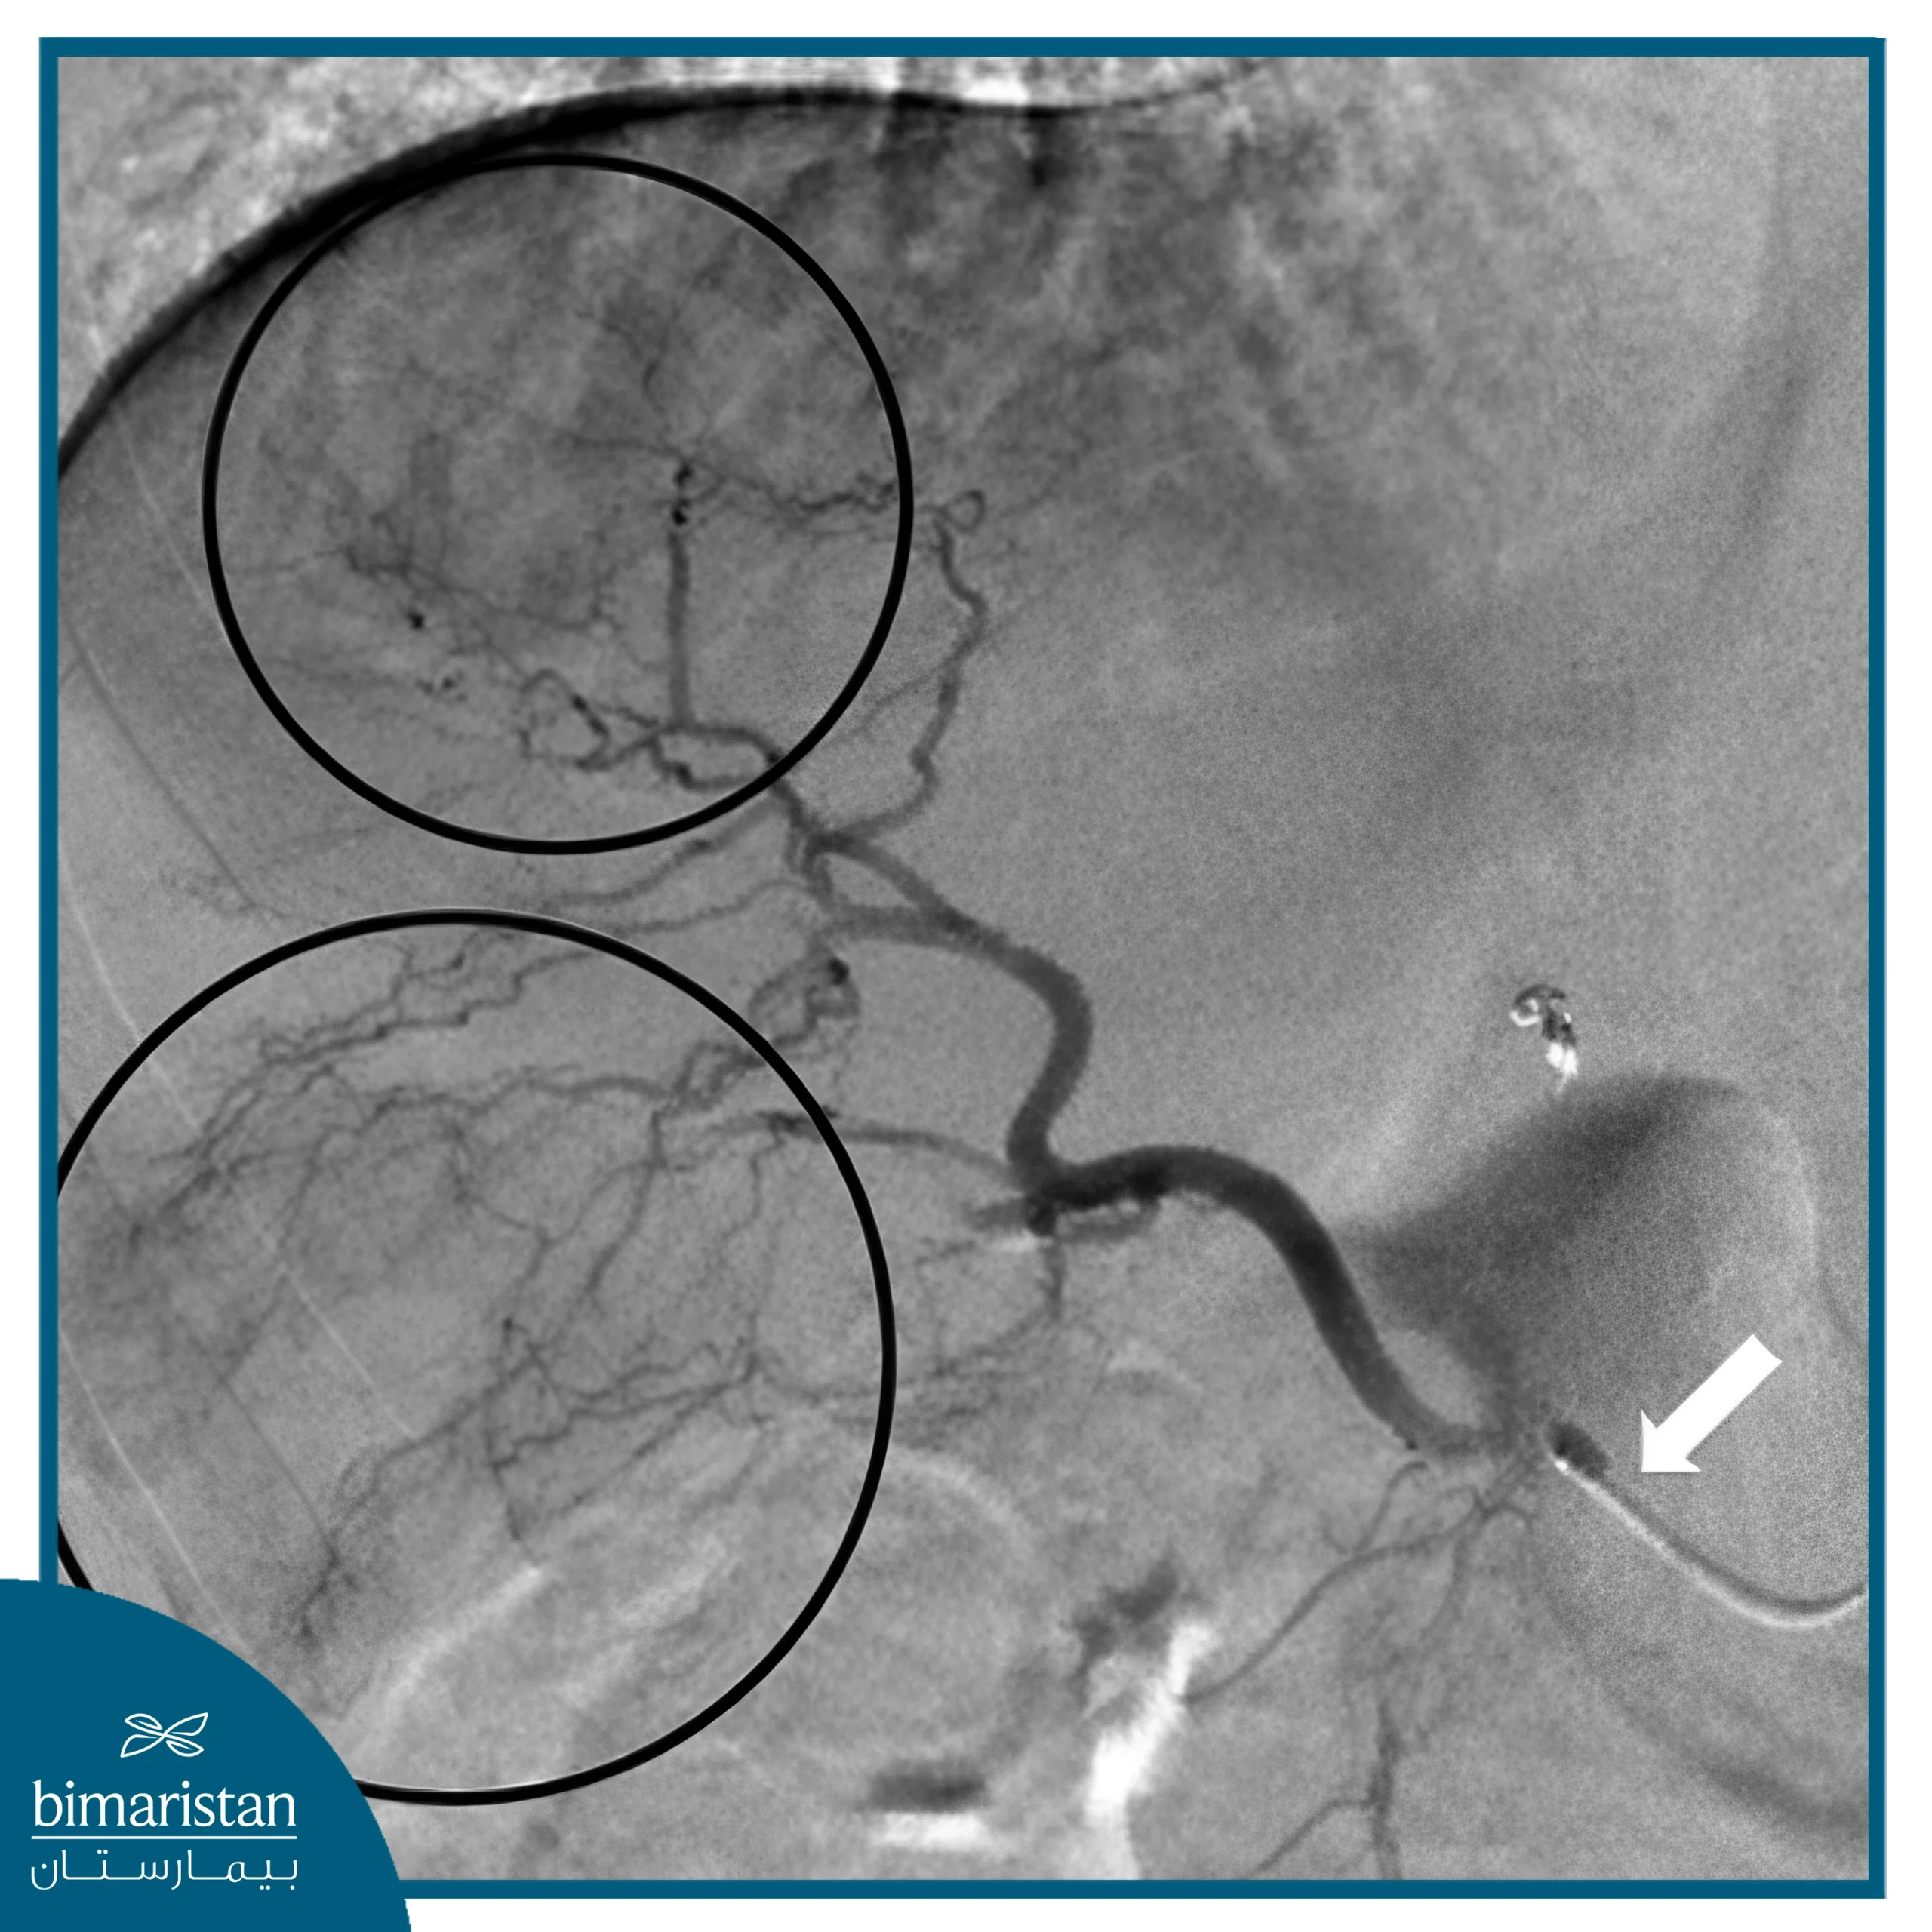

يُعَدّ تصوير الأوعية بالطرح الرقمي (DSA) خطوة جوهرية في التخطيط لإجراء التخثير الشعاعي، إذ يوفّر صورًا عالية الدقة للتشريح الوعائي ويُمكّن الطبيب من تحديد الشرايين المغذية للورم بدقة فائقة. كما يساعد في كشف الفروع الوعائية الجانبية غير المرغوبة التي قد تُسهم في انتقال الجزيئات المشعة إلى أعضاء سليمة مثل المعدة أو الأمعاء، إضافة إلى دوره الأساسي في تقييم وجود تحويلات وعائية (Shunts) بين الكبد والرئتين. ويساهم هذا التقييم في ضبط الجرعة الإشعاعية وتجنب المضاعفات الرئوية، مما يجعل DSA خطوة لا غنى عنها لضمان نجاح العلاج وسلامته.

خلال التصوير الوعائي الأولي، يقوم الطبيب بسد فروع الشرايين غير المرغوبة لمنع انتقال الجزيئات المشعة إلى الأنسجة السليمة.

قبل البدء بالحقن العلاجي، يقوم اختصاصي الأشعة التداخلية بإغلاق الفروع الوعائية غير المرغوبة التي قد تنقل الجزيئات المشعة إلى أعضاء سليمة مثل المعدة أو البنكرياس أو الاثني عشر. ويتم ذلك باستخدام مواد انصمام صغيرة أو لفائف معدنية دقيقة تهدف إلى منع تسرب الجزيئات المشعة خارج الورم. وتُعد هذه الخطوة ضرورية لحماية الأنسجة السليمة وضمان أن يتركز تأثير العلاج داخل الورم فقط.